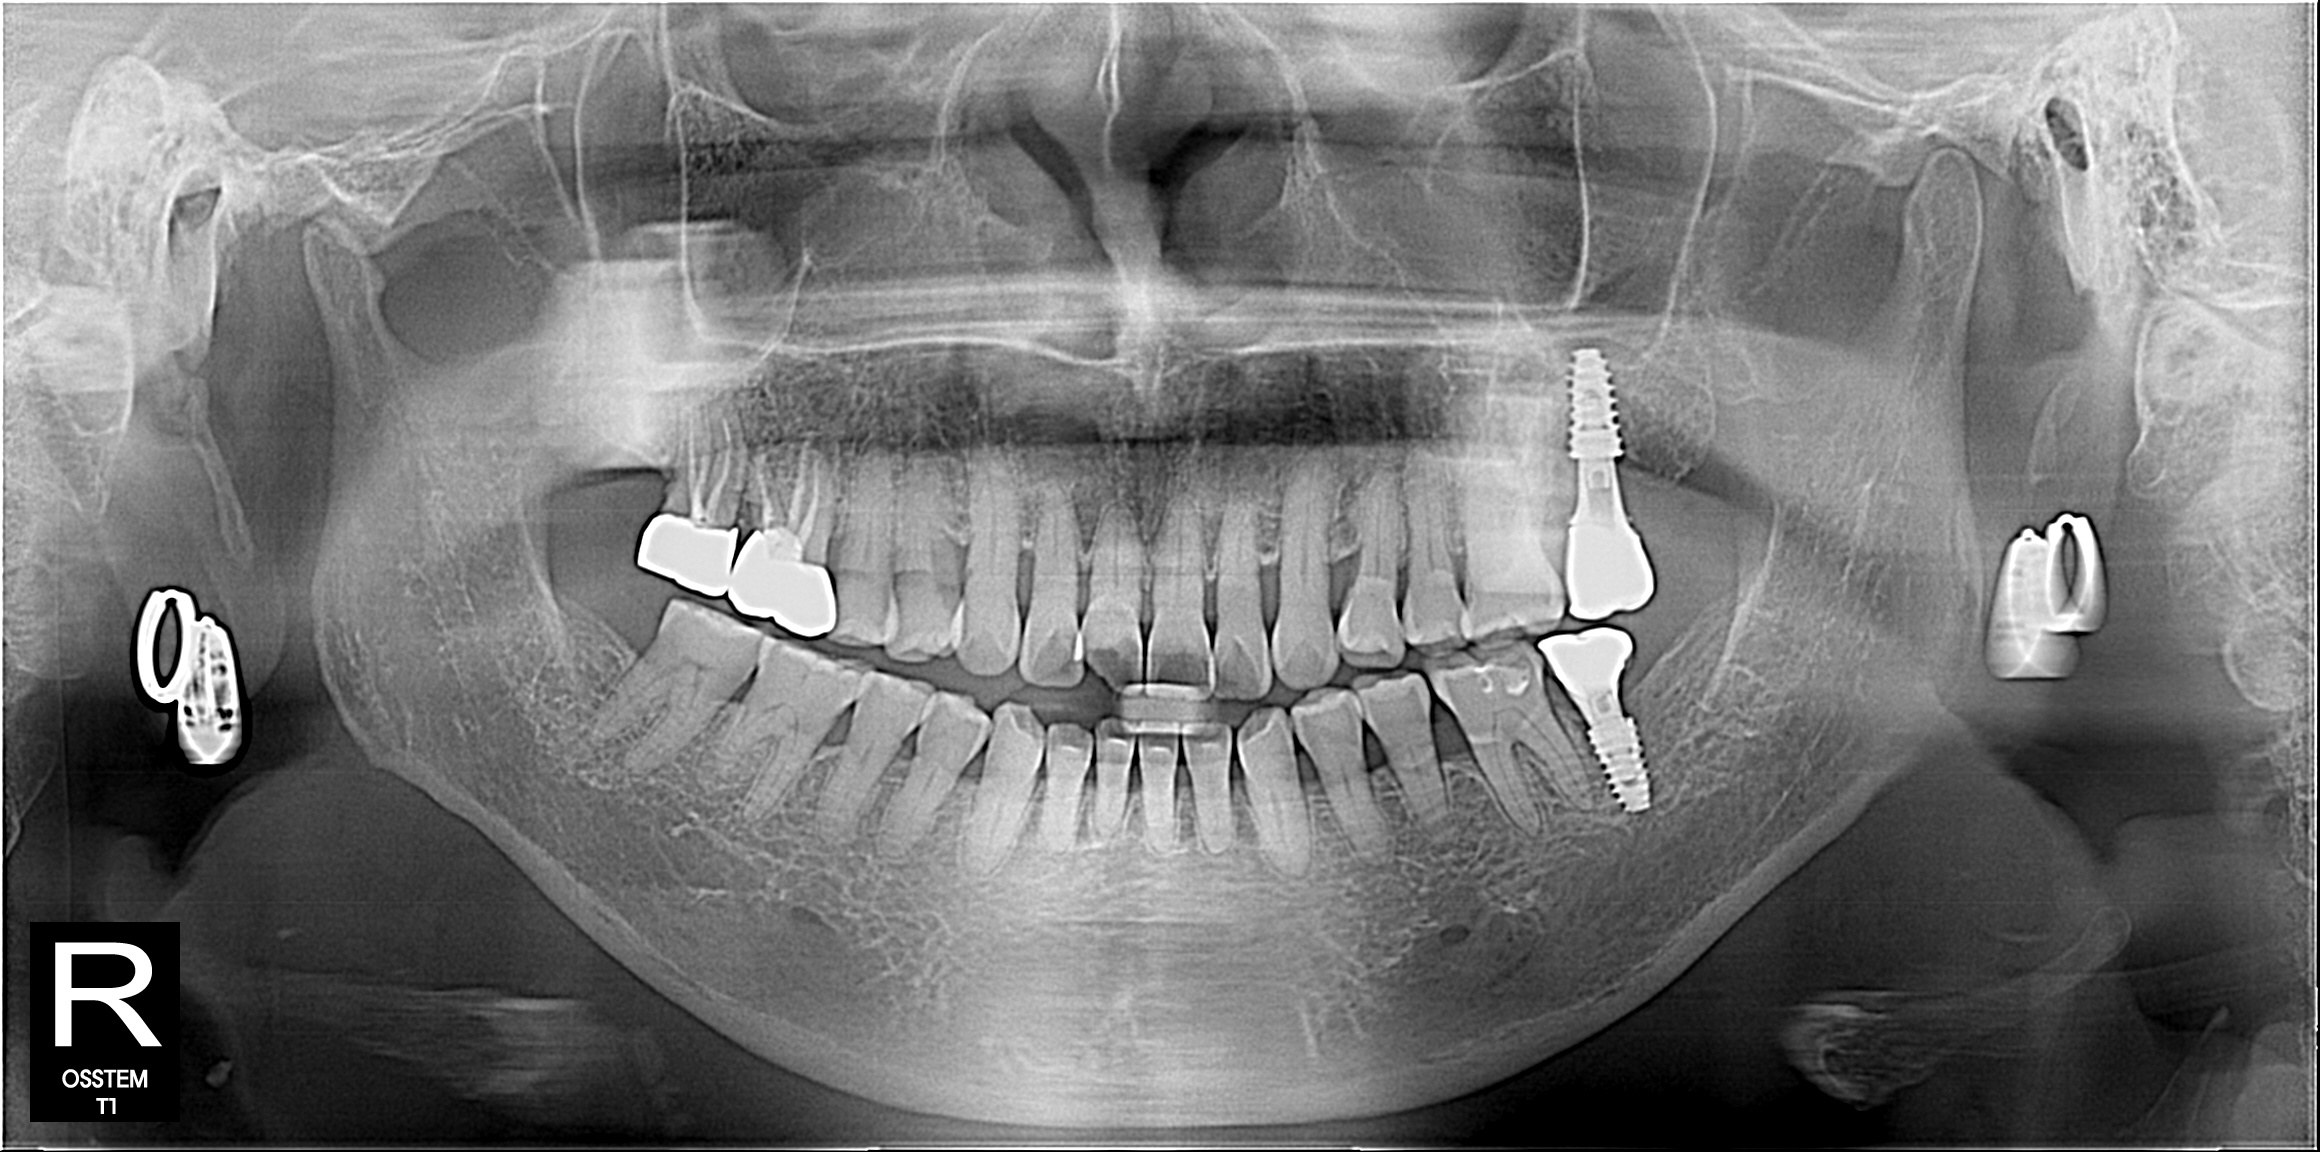

일반진료

BEFORE & AFTER